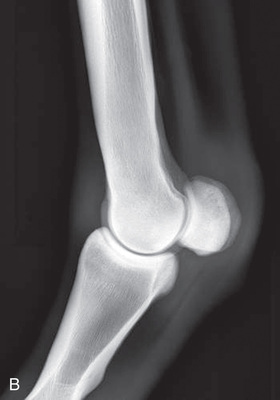

| Elbow joint | Cranioproximal-caudodistal (CrPr-CdDi)—standing | Craniocaudal (CrCd) |

| Mediolateral standing (ML) | Lateral (L) | |

The elbow joint is difficult to radiograph while the animal is in a standing position because of its proximity to the ventral body wall. The use of general anesthesia is preferred if possible. Because of the increased thickness of the limb, higher-capacity x-ray equipment is required.

With the patient standing, the mediolateral view is the easiest positioning for the elbow and is often suitable for a portable x-ray unit.

| Elbow joint | CdCr (Standard) | Caudoproximal-craniodistal- standing (CdPr-CrDi) | Weight-bearing with limbs evenly on ground and cassette against cranial aspect of joint at angle to the x-ray beam. | Caudal to joint; parallel to ground so beam perpendicular to radius. |

| Lateral (Standard) | Lateromedial standing (LM) | Weight-bearing with limbs evenly on ground; cassette against medial aspect of joint at angle to the x-ray beam. | 90 degrees lateral to MSP, parallel to ground on either the elbow joint or olecranon if required. | |